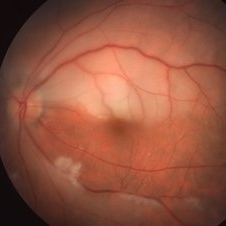

Central Retinal Artery Occlusion

61-year-old male patient with acute CRAO OS demonstrating a hyperemic optic disc with a couple of peripapillary hemorrhages, generalized arteriolar narrowing, a cherry-red spot in the macula, and retinal whitening surrounding the fovea; VA= LP.

Imaging device: Topcon VT-50

Condition/keywords: central retinal artery occlusion (CRAO), cherry red spot, retinal whitening